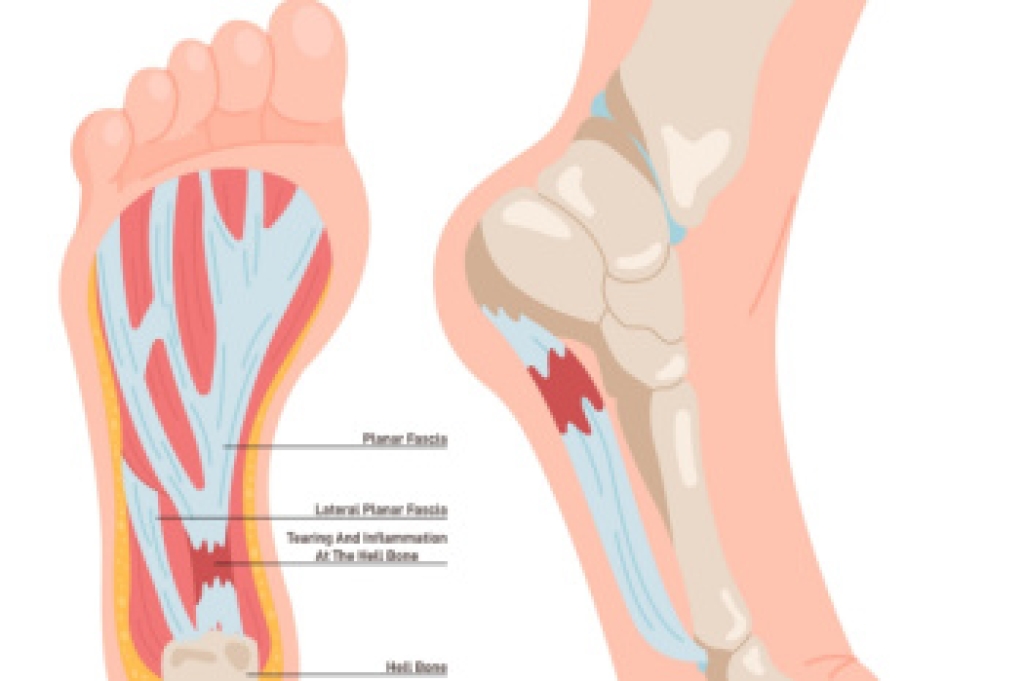

What Is Plantar Fasciitis?

Plantar fasciitis is the inflammation of the thick band of tissue that runs along the bottom of your foot, known as the plantar fascia, and causes mild to severe heel pain.

What Causes Plantar Fasciitis?

- Repeated stretching and tearing of the plantar fascia